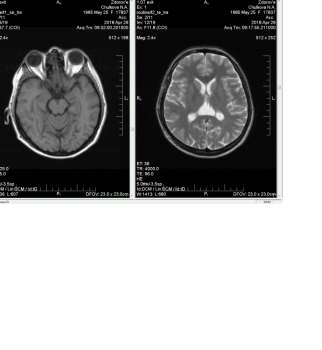

Добрый вечер! Будьте добры ,подскажите, в 2013 году проходила МРТ , обнаружена киста арахноидальная зчя ,с размерами 23*18*25mm, невролог сказал врожденная, в июне 2017 обратилась к неврологу из-за головных болей, потери концентрации, усталости , колящих болей в глазах( резких и быстро проходящих), сделала повторное МРТ киста увеличилась в размере 28*18*28mm ,подскажите насколько это серьезно, какие последствия, нужно ли оперативное вмешательство , мне 30 лет. Заранее буду очень благодарна за компетентный ответ! Спасибо!

С 2015 г мучают головные боли,мрт от 2015 в зчя определяется арахноиндальная киста размером 3*37*18мм,прошла курс лечения,но боли не проходили,в 2016 году повторно сделала мрт,отмечается арахноиндальная киста зчя размером 30*40*20мм,оттесняя и поддавливая отделы полушария мозжечка,все это время я сижу на таблетках которые назначил врач и обезбаливающих,в последнее время повышается ар.давление до 170/100,но боли не проходят.Может ли киста влиять на головные боли?

Здравствуйте. Наталья 32 года. Исследования МРТ дало такие результаты.Имеется также киста промежуточного паруса с максимальным поперечным размером ликворной полости до 3,2 см, деформирующая задние отделы боковых желудочков.В шишковидном теле имеются микроочаговые изменения МР-сигнала с четкими контурами, размером до 0,2 см (более вероятно микрокисты). Пошла на МРТ в связи с потерей сознания. Симптомы которые у меня уже давно- головная боль, туман в глазах, неустойчивая походка, сонливость , быстрая утомляемость, двление в глазах, ночью вздрагивание(ощущение падения) Также исследование офтальмолога показало ангиопатию сетчатки глаз.

Подскажите связанны ли эти симптомы с кистой? Как избежать потери сознания. Врачи прописали- 10 дней актавигин уколами внутривенно, возобрал. Поможет ли это? За ранее спасибо.